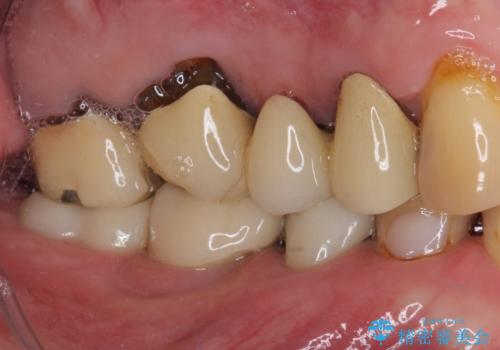

歯肉が退縮したことで見えていた歯根もセラミッククラウンで覆うことができ、清掃性も改善されました。

仮歯に変えた後、咬合力に耐えることを目的に強化セラミッククラウンにて補綴することとしました。